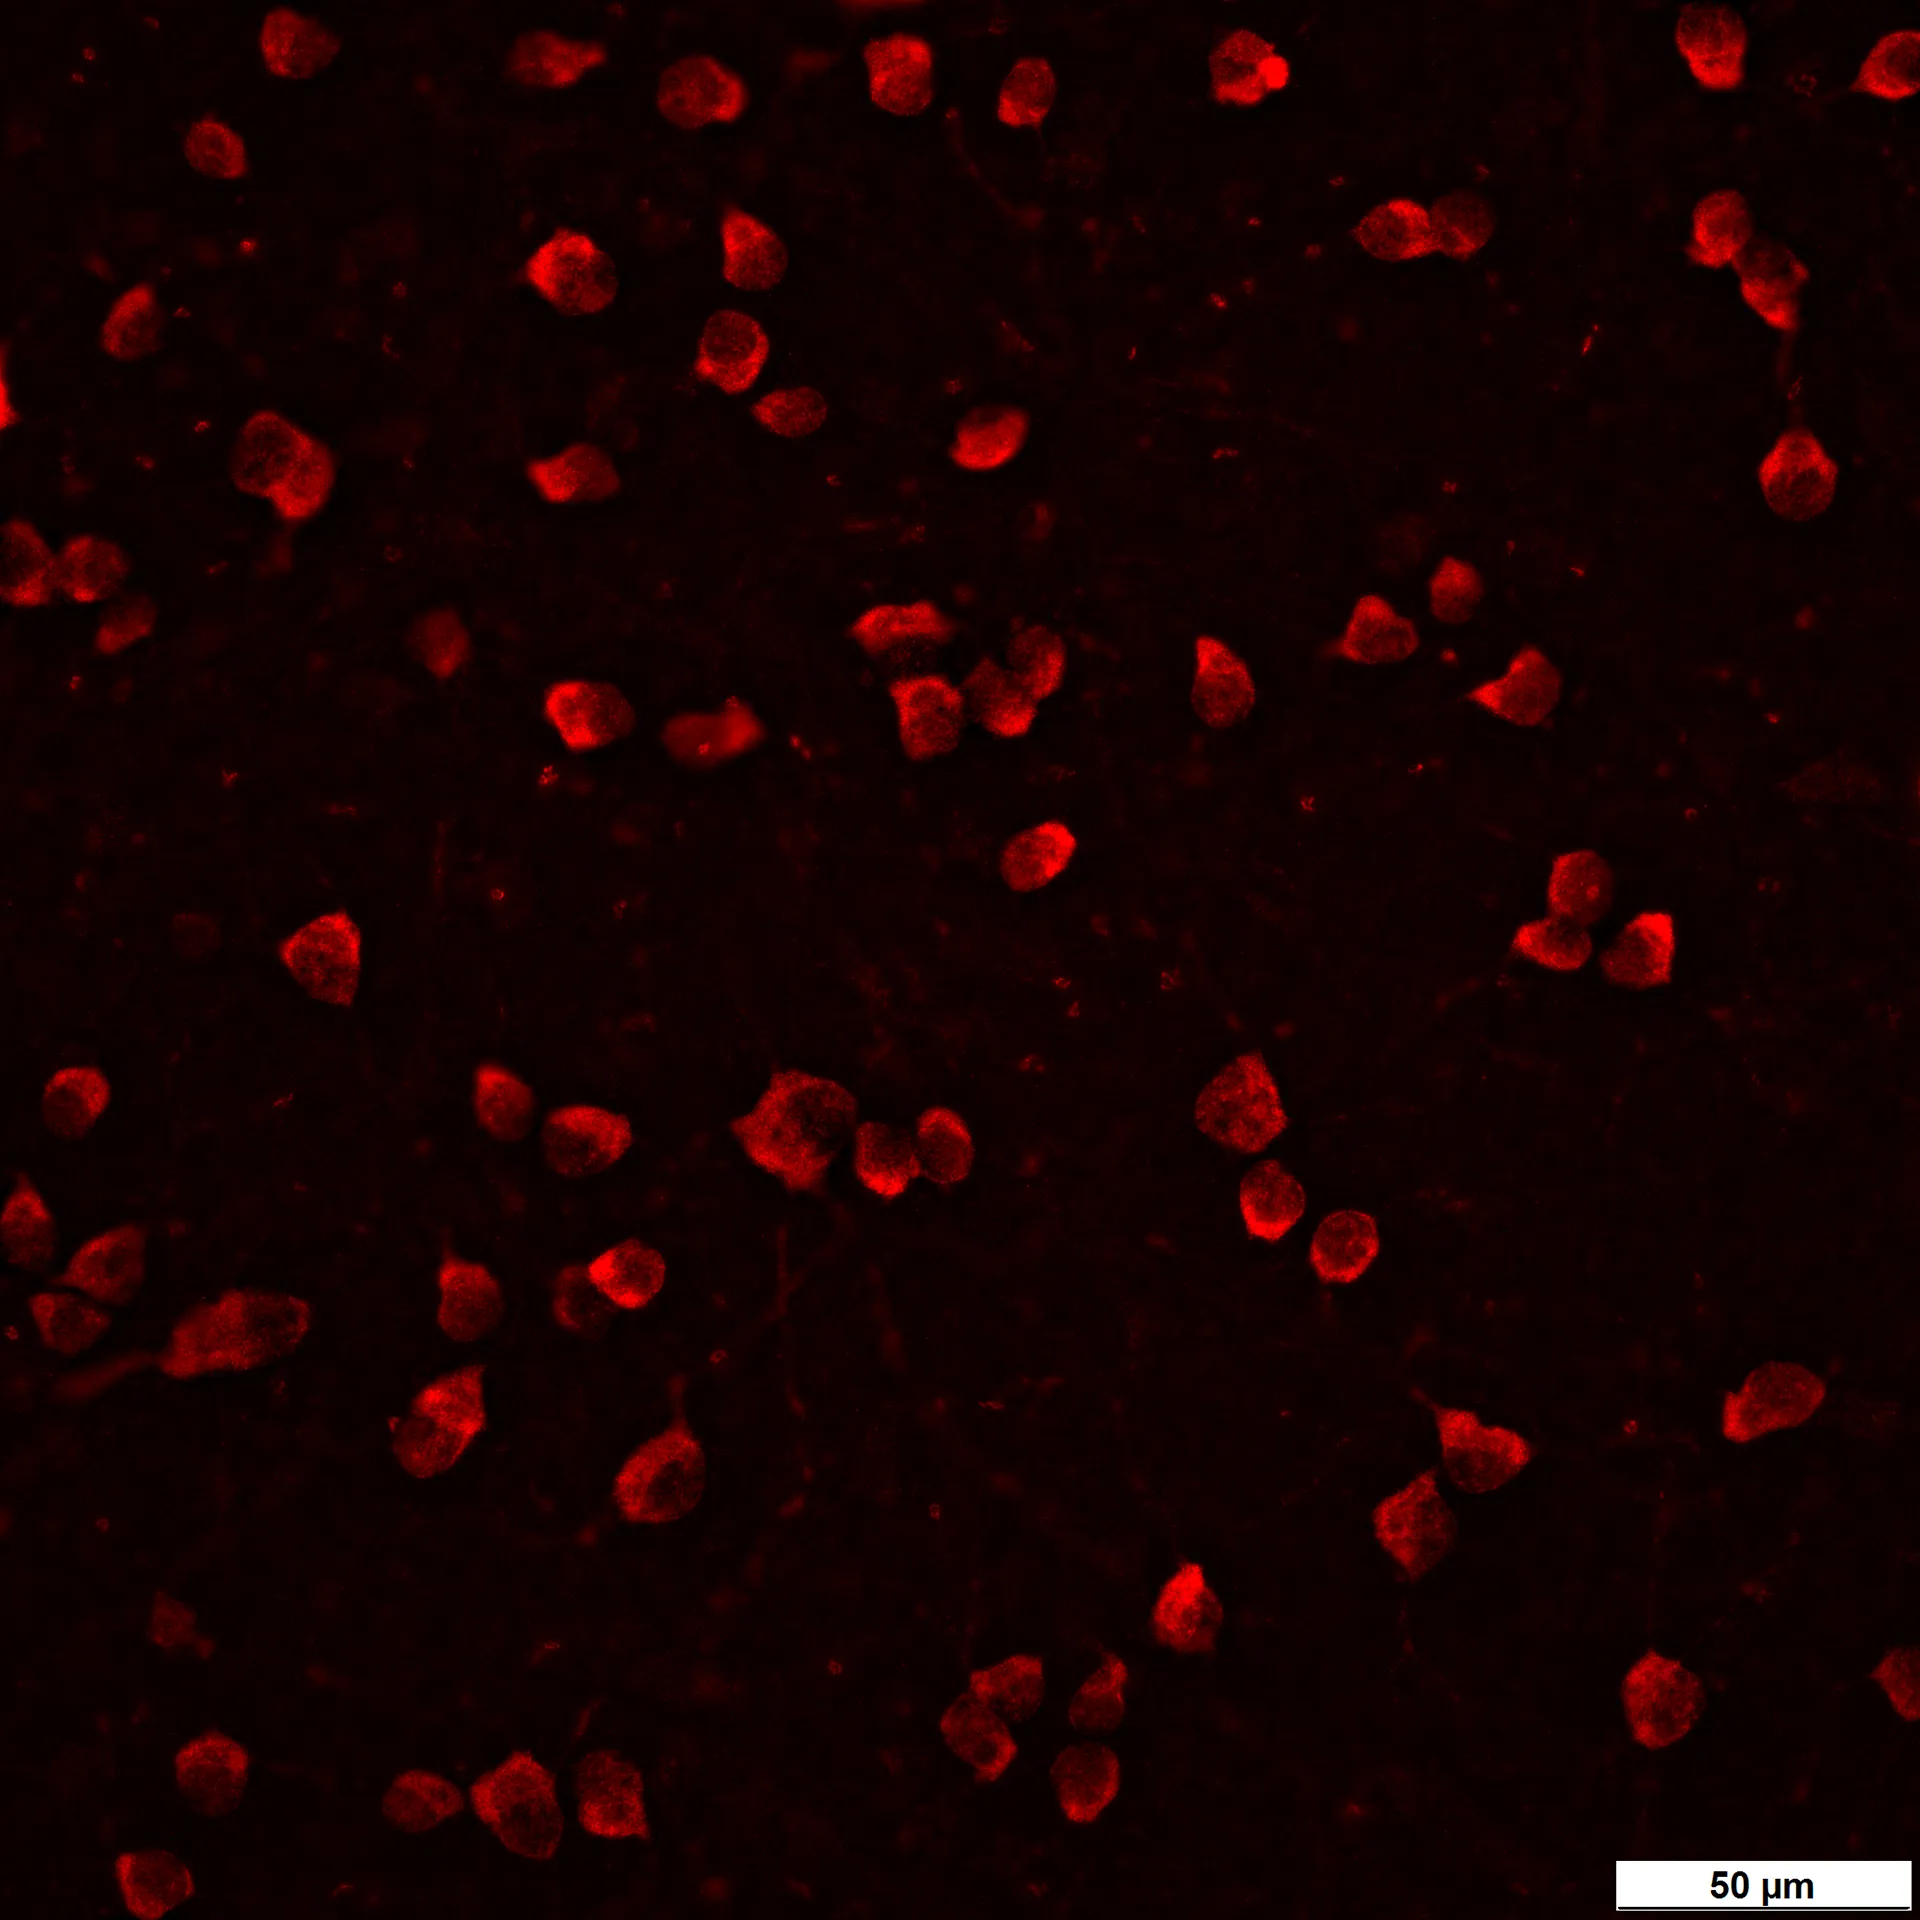

The magnetic microbead-induced model was first described by Samsel and colleagues in 2011. The elevated IOP is induced by injecting magnetic particles into the mouse or rat anterior chamber to obstruct aqueous outflow, leading to a gradual and sustained increase in intraocular pressure (IOP). The episcleral vein photocoagulation model, developed by Shareef and colleagues in 1995, induces IOP elevation through targeted coagulation of episcleral veins, creating a chronic hypertensive environment that closely mimics the gradual progression of glaucoma in humans. Both methods effectively mimic glaucomatous damage, allowing for the assessment of neuroprotective and IOP-lowering therapies. In addition, these models are particularly useful for studying chronic retinal ganglion cell (RGC) degeneration and optic nerve damage.

– Quantitative estimation of RGCs